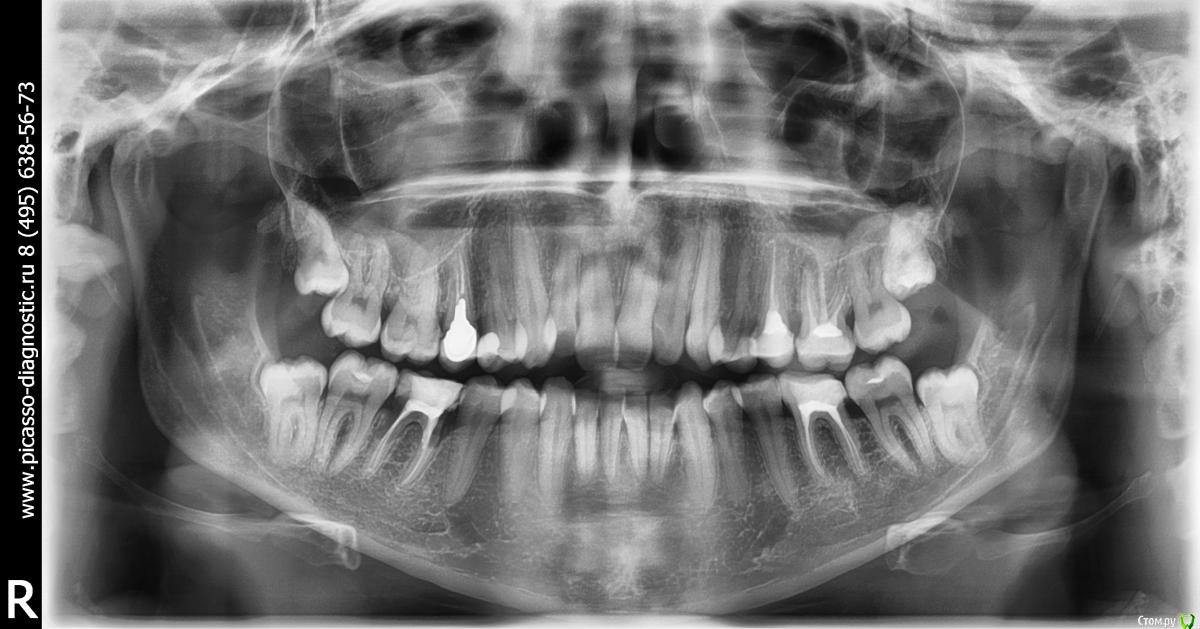

viktori Опубликовано 23 ноября, 2015 Поделиться Опубликовано 23 ноября, 2015 (изменено) Добрый день.Пожалуйста посоветуйте. Мне пять дней назад установили брекеты на верхнюю челюсть, но только на 8 зубов, до 5-ки, на обеих пятерках стоят коронки, одна временная специально для установки брекетов. Скученность зубов сильная, но врач сказал, что у меня там от пятерки и дальше все нормально и поэтому не надо на них ставить брекеты, я очень переживаю, так как читала, что должен формироваться прикус и поэтому все зубы должны быть выровнены, а в моем случае еще и нет места для выравнивания зубов если не двигать все, подскажите, есть ли такая практика и возможно ли выравнивание зубов если брекеты будут установлены только на 8 зубов.Дополнительно прикрепляю снимок. Изменено 23 ноября, 2015 пользователем viktori Ссылка на комментарий

Caries Опубликовано 26 ноября, 2015 Поделиться Опубликовано 26 ноября, 2015 Фиксация частичной аппаратуры приведет к работе в области задействованных зубов. При этом перемещение зубов будет непредсказуемым. Нужен анализ моделей челюстей, фотографий, рентгеновских снимков и потом лечение брекет-системой...полноценной Ссылка на комментарий